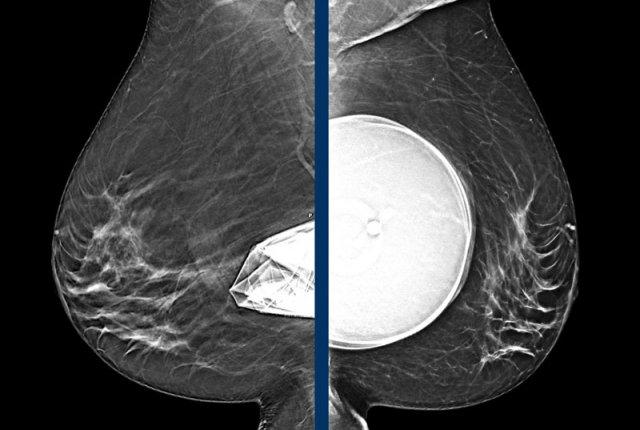

Cùng một bệnh nhân trước và sau khi đặt túi ngực trước cơ ngực (prepectoral).

Đặc biệt, túi ngực đặt trước cơ ngực có thể làm giảm khả năng đánh giá trên nhũ ảnh.

Tuy nhiên, chụp nhũ ảnh thông thường và chụp cắt lớp tổng hợp 3D (3D tomosynthesis) vẫn có thể thực hiện tốt và thực tế có giá trị tiên đoán dương tính (PPV) cao nhất trong việc phát hiện silicon ngoài bao xơ.